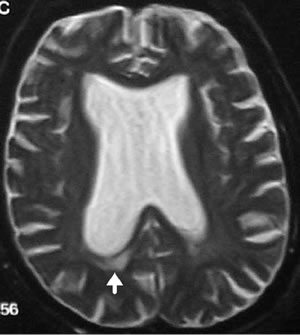

脑脊液动力学百年经典理论争议-国际小儿神外教科书教授谈脑积水新病理机制